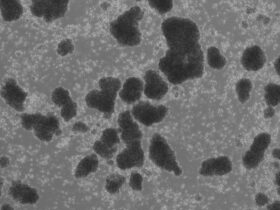

To address these questions, the researchers analyzed blood plasma samples from 520 individuals, including people with diagnosed Alzheimer’s, people with mild cognitive impairment, and healthy controls. The individuals were volunteer research participants at the NIA-funded Alzheimer’s Disease Research Centers in Kansas and California, where they were seen for annual visits. Using mass spectrometry and machine learning, the researchers were able to characterize changes in protein structure associated with genetic risk for Alzheimer’s—specifically in variants of the ApoE gene. They also connected disease-related changes to the severity of neuropsychiatric symptoms in males and females, observing distinct structural patterns by sex.

The research team then used machine learning to develop a diagnostic panel of three proteins—C1QA, CLUS, and ApoB—representing Alzheimer’s-associated structural changes. They found that the panel could accurately distinguish between Alzheimer’s, mild cognitive impairment, and healthy controls, and it could distinguish disease stages and track progression of disease over time.